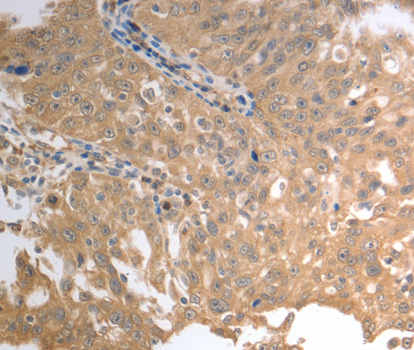

Immunohistochemistry of paraffin-embedded rat liver using SLC1A4 antibody.

Immunohistochemistry of paraffin-embedded human prostate using SLC1A4 antibody.

Immunohistochemistry of paraffin-embedded human esophagus using SLC1A4 antibody.